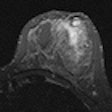

Breast MRI displays viability for new indications